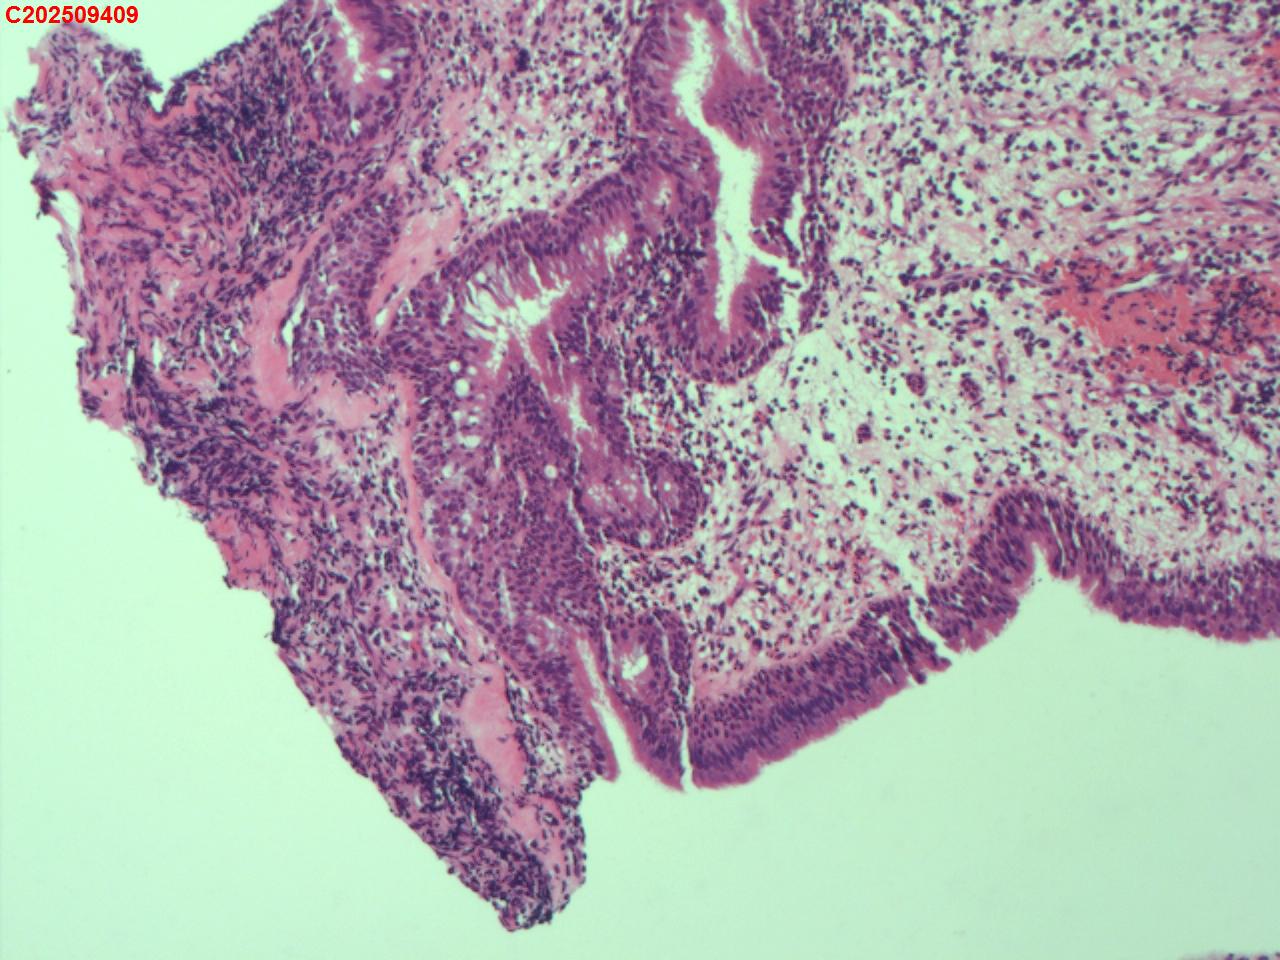

性别年龄62岁临床诊断社区获得性肺炎,肺占位性病变带除外

一般病史胸部CT:双肺可见多发斑片状、结节状高密度影,右肺上叶及左肺下叶病灶内见多发空洞,右侧少量胸腔积液。

标本名称纤支镜咬检

大体所见纤支镜:气管通畅,隆突锐利。右肺主支气管通畅,右肺上叶见少量痰液,负压吸引后见上叶开口干酪坏死物质附着,上叶各段级支气管通畅未见新生物及坏死物质,中叶、下叶背段支气管通畅,下叶基底段见新生物阻塞气道,粘膜无充血。左肺主支气管、上叶、下叶及各段级支气管通畅,粘膜无充血,未见新生物及坏死物。

考虑:支气管炎性息肉